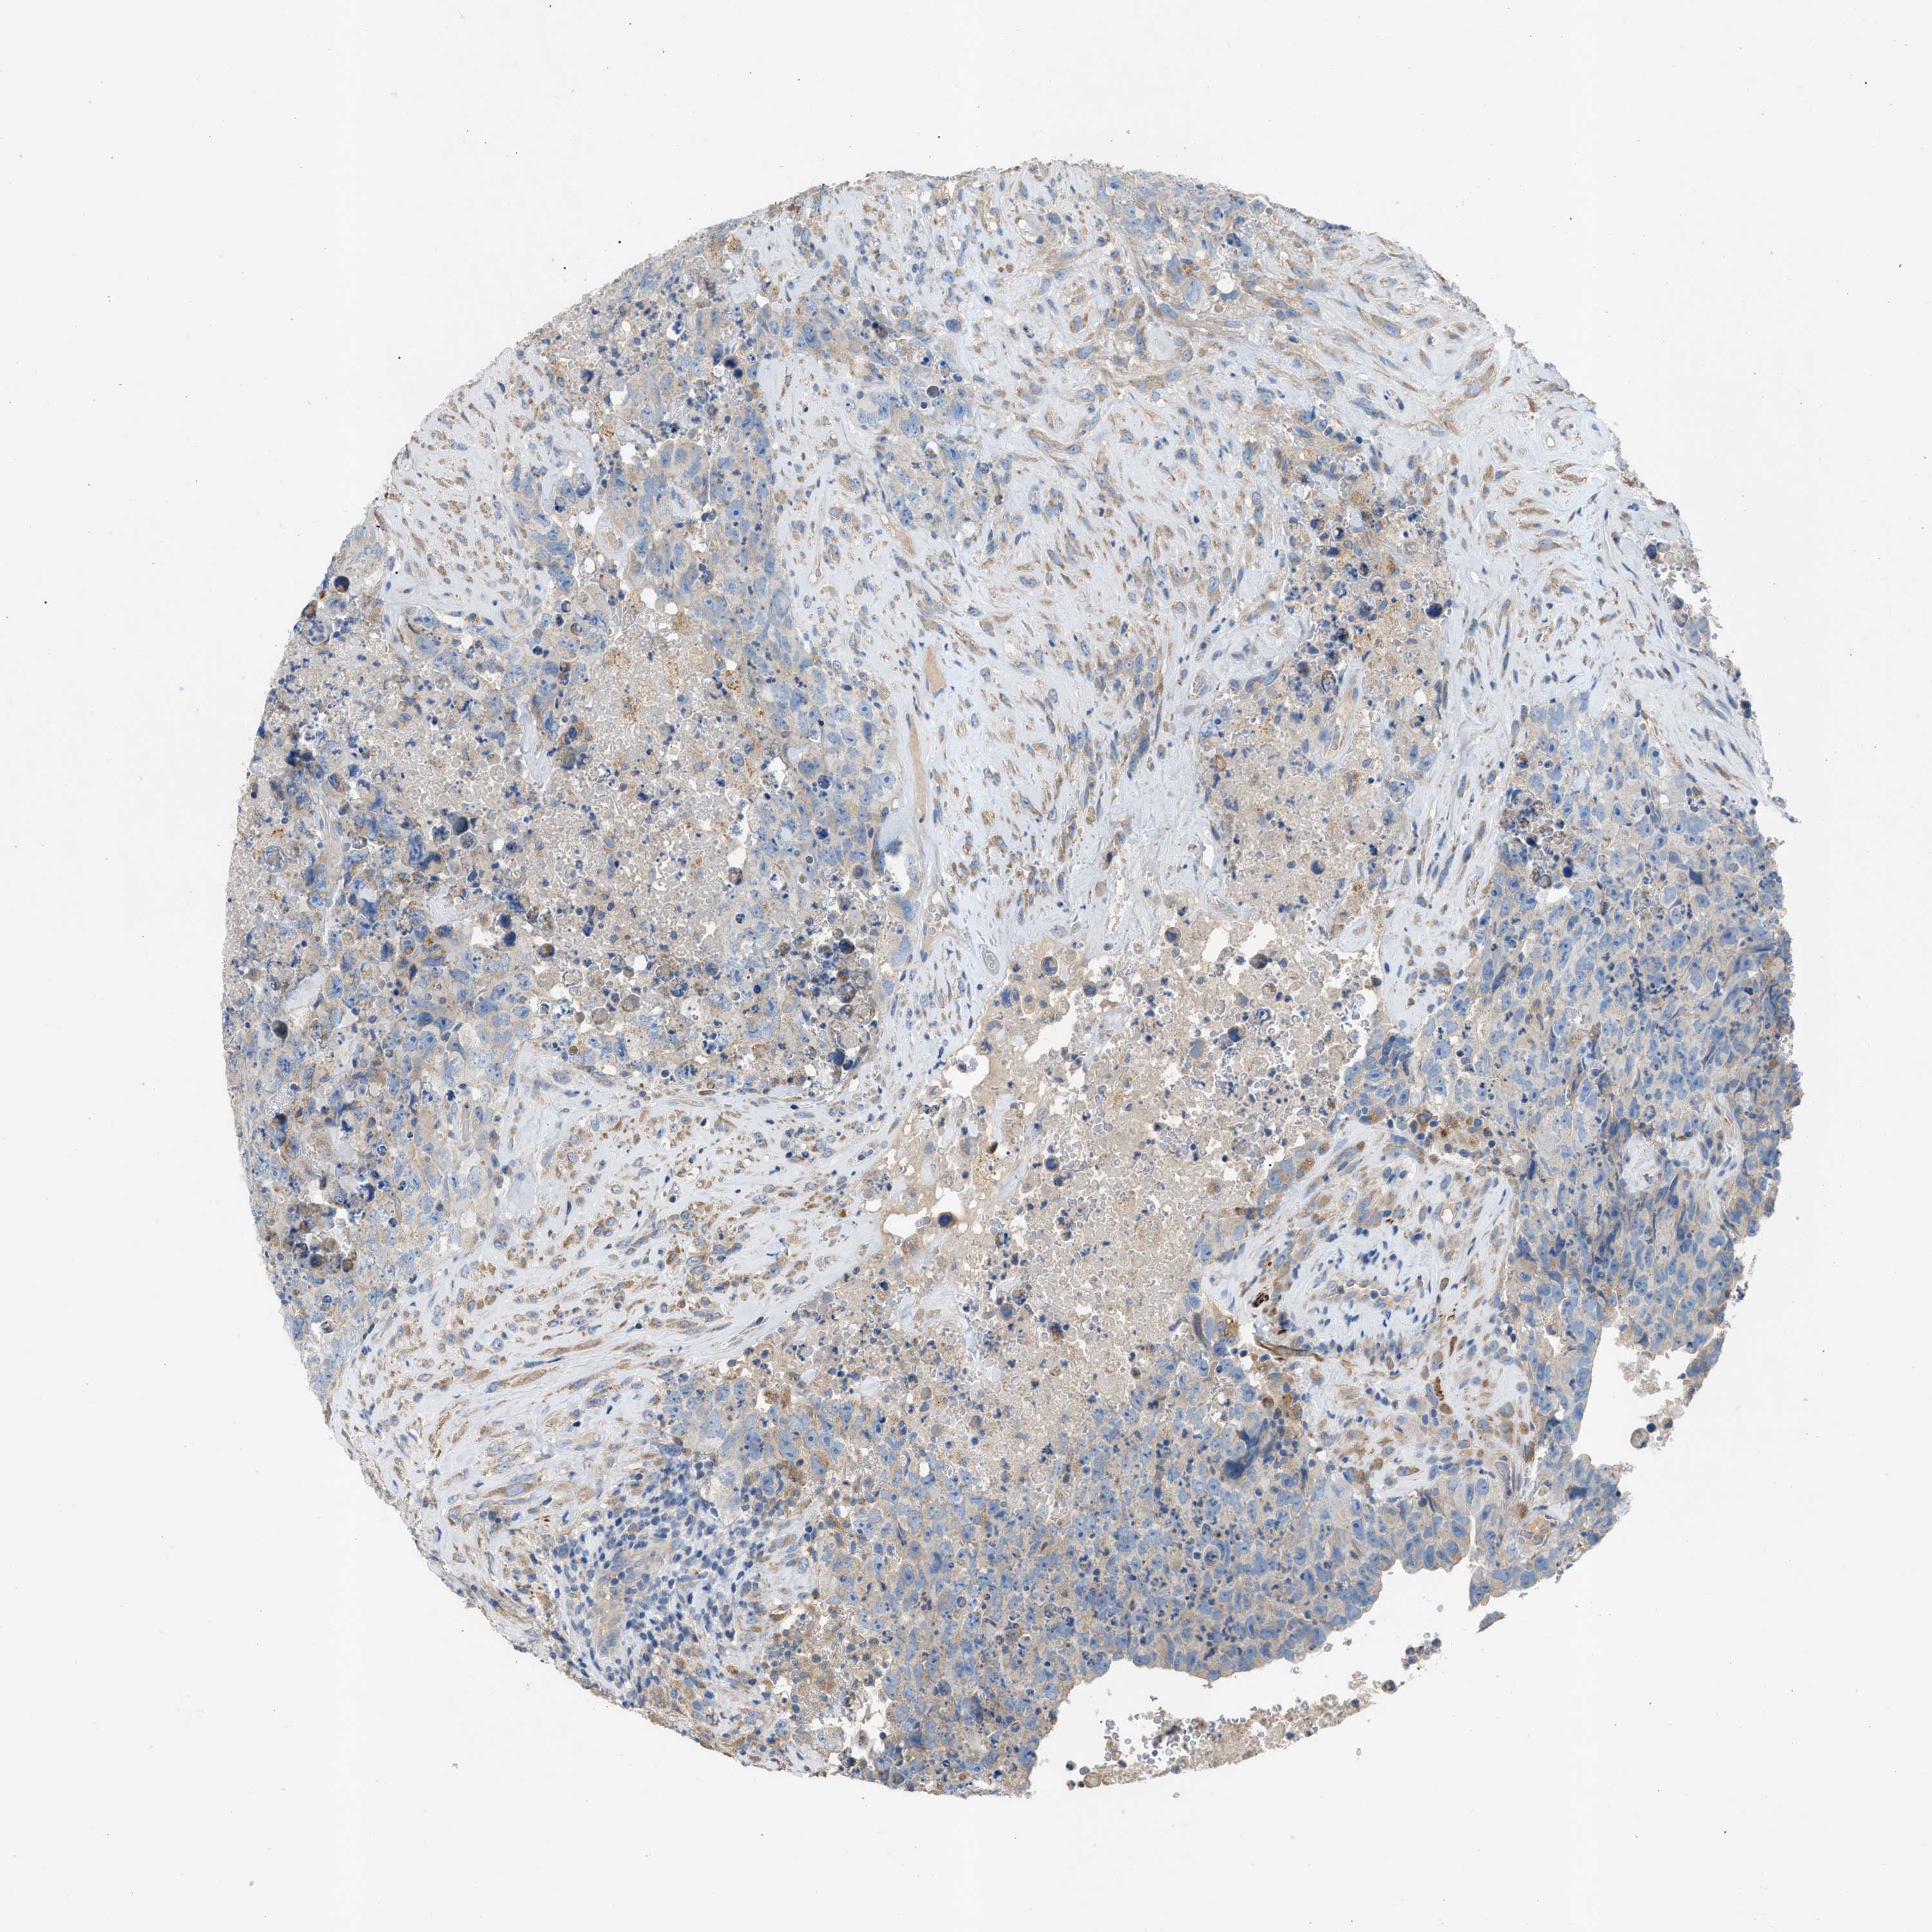

TESTIS CANCER - Protein expressioni

A mouse-over function shows sample information and annotation data. Click on an image to view it in a full screen mode. Samples can be filtered based on level of antibody staining by selecting one or several of the following categories: high, medium, low and not detected. The assay and annotation is described here.

Note that samples used for immunohistochemistry by the Human Protein Atlas do not correspond to samples in the TCGA dataset.

Antibody stainingi

Antibody staining in the annotated cell types in the current human tissue is reported as not detected, low, medium, or high, based on conventional immunohistochemistry profiling in selected tissues. This score is based on the combination of the staining intensity and fraction of stained cells.

Each image is clickable and will lead to virtual microscopy that enables deeper exploration of all samples and also displays staining intensity scores, fraction scores and subcellular localization as well as patient and tissue information for each sample.

Antibody HPA021666

Antibody HPA026716

Staining

High

Medium

Low

Not detected

Intensity

Strong

Moderate

Weak

Negative

Quantity

>75%

75%-25%

<25%

None

Location

Nuclear

Cytoplasmic/membranous

Cytoplasmic/membranous,nuclear

Carcinoma, Embryonal, NOS

Seminoma, NOS